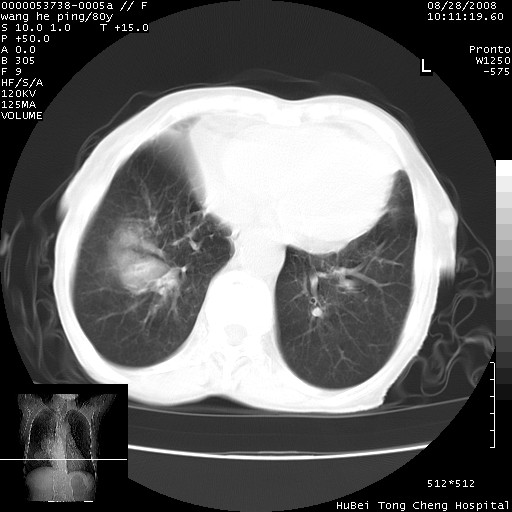

以下是引用黑白光影在2008-8-28 22:33:00的发言:[br]右肺中央型肺癌伴阻塞性肺炎,肺癌肺转移。

以下是引用lshx在2008-8-28 22:06:00的发言:[br]1.右肺中心型肺癌伴阻塞性肺炎,不除外双 肺早期转移。[br]2.心包积液。

以下是引用随光逐影在2008-8-29 7:40:00的发言:[br]1)右肺中心型肺癌伴阻塞性肺炎,肺内转移。2)心包积液(少量)。

以下是引用wqs571018在2008-8-28 21:56:00的发言:[br]右肺中心型肺癌伴阻塞性肺炎可能。

以下是引用liuyue在2008-8-28 22:46:00的发言:[br]1.右肺中心型肺癌伴阻塞性肺炎。[br]2.心包积液(少量)。